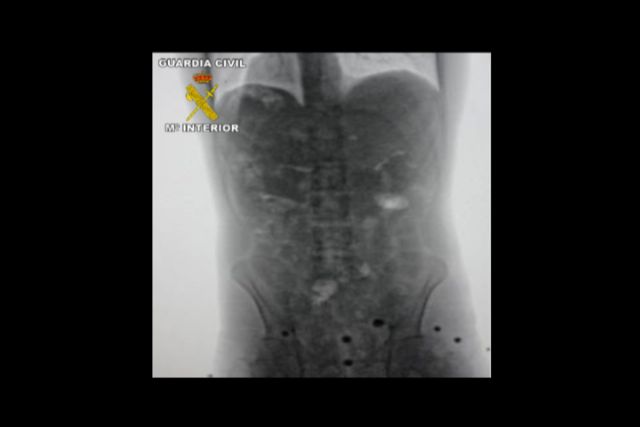

La investigación se inició en febrero de 2012 cuando una persona denunció la muerte de un vecino de Águilas (Murcia), que presuntamente había sido contratado por otras personas para que realizara viajes a Bolivia con la intención de introducir en España cocaína en el interior de su cuerpo. Esta persona falleció en Bolivia porque dos de los envases de cocaína que transportaba se rompieron.

Tras las primeras pesquisas se obtuvieron indicios que permitieron judicializar la investigación, que dio sus primeros frutos unos meses más tarde cuando la Guardia Civil detuvo a cuatro personas en Madrid que trasladaban hasta Murcia más de medio kilo de cocaína de gran pureza. Seguidamente, en Barajas, se interceptó y detuvo a otras dos personas que realizaban la misión de mulas, ya que importaban desde Bolivia un kilo de cocaína cada uno en el interior de su cuerpo.

Por otro lado, en la prisión de Palmasola, ubicada en Santa Cruz de la Sierra, se procedió a tomar declaración a una interna de origen español que fue captada por la organización investigada y, posteriormente, detenida cuando pretendía salir del país con destino a España como mula, ya que transportaba en el interior de su cuerpo un kilo de cocaína.